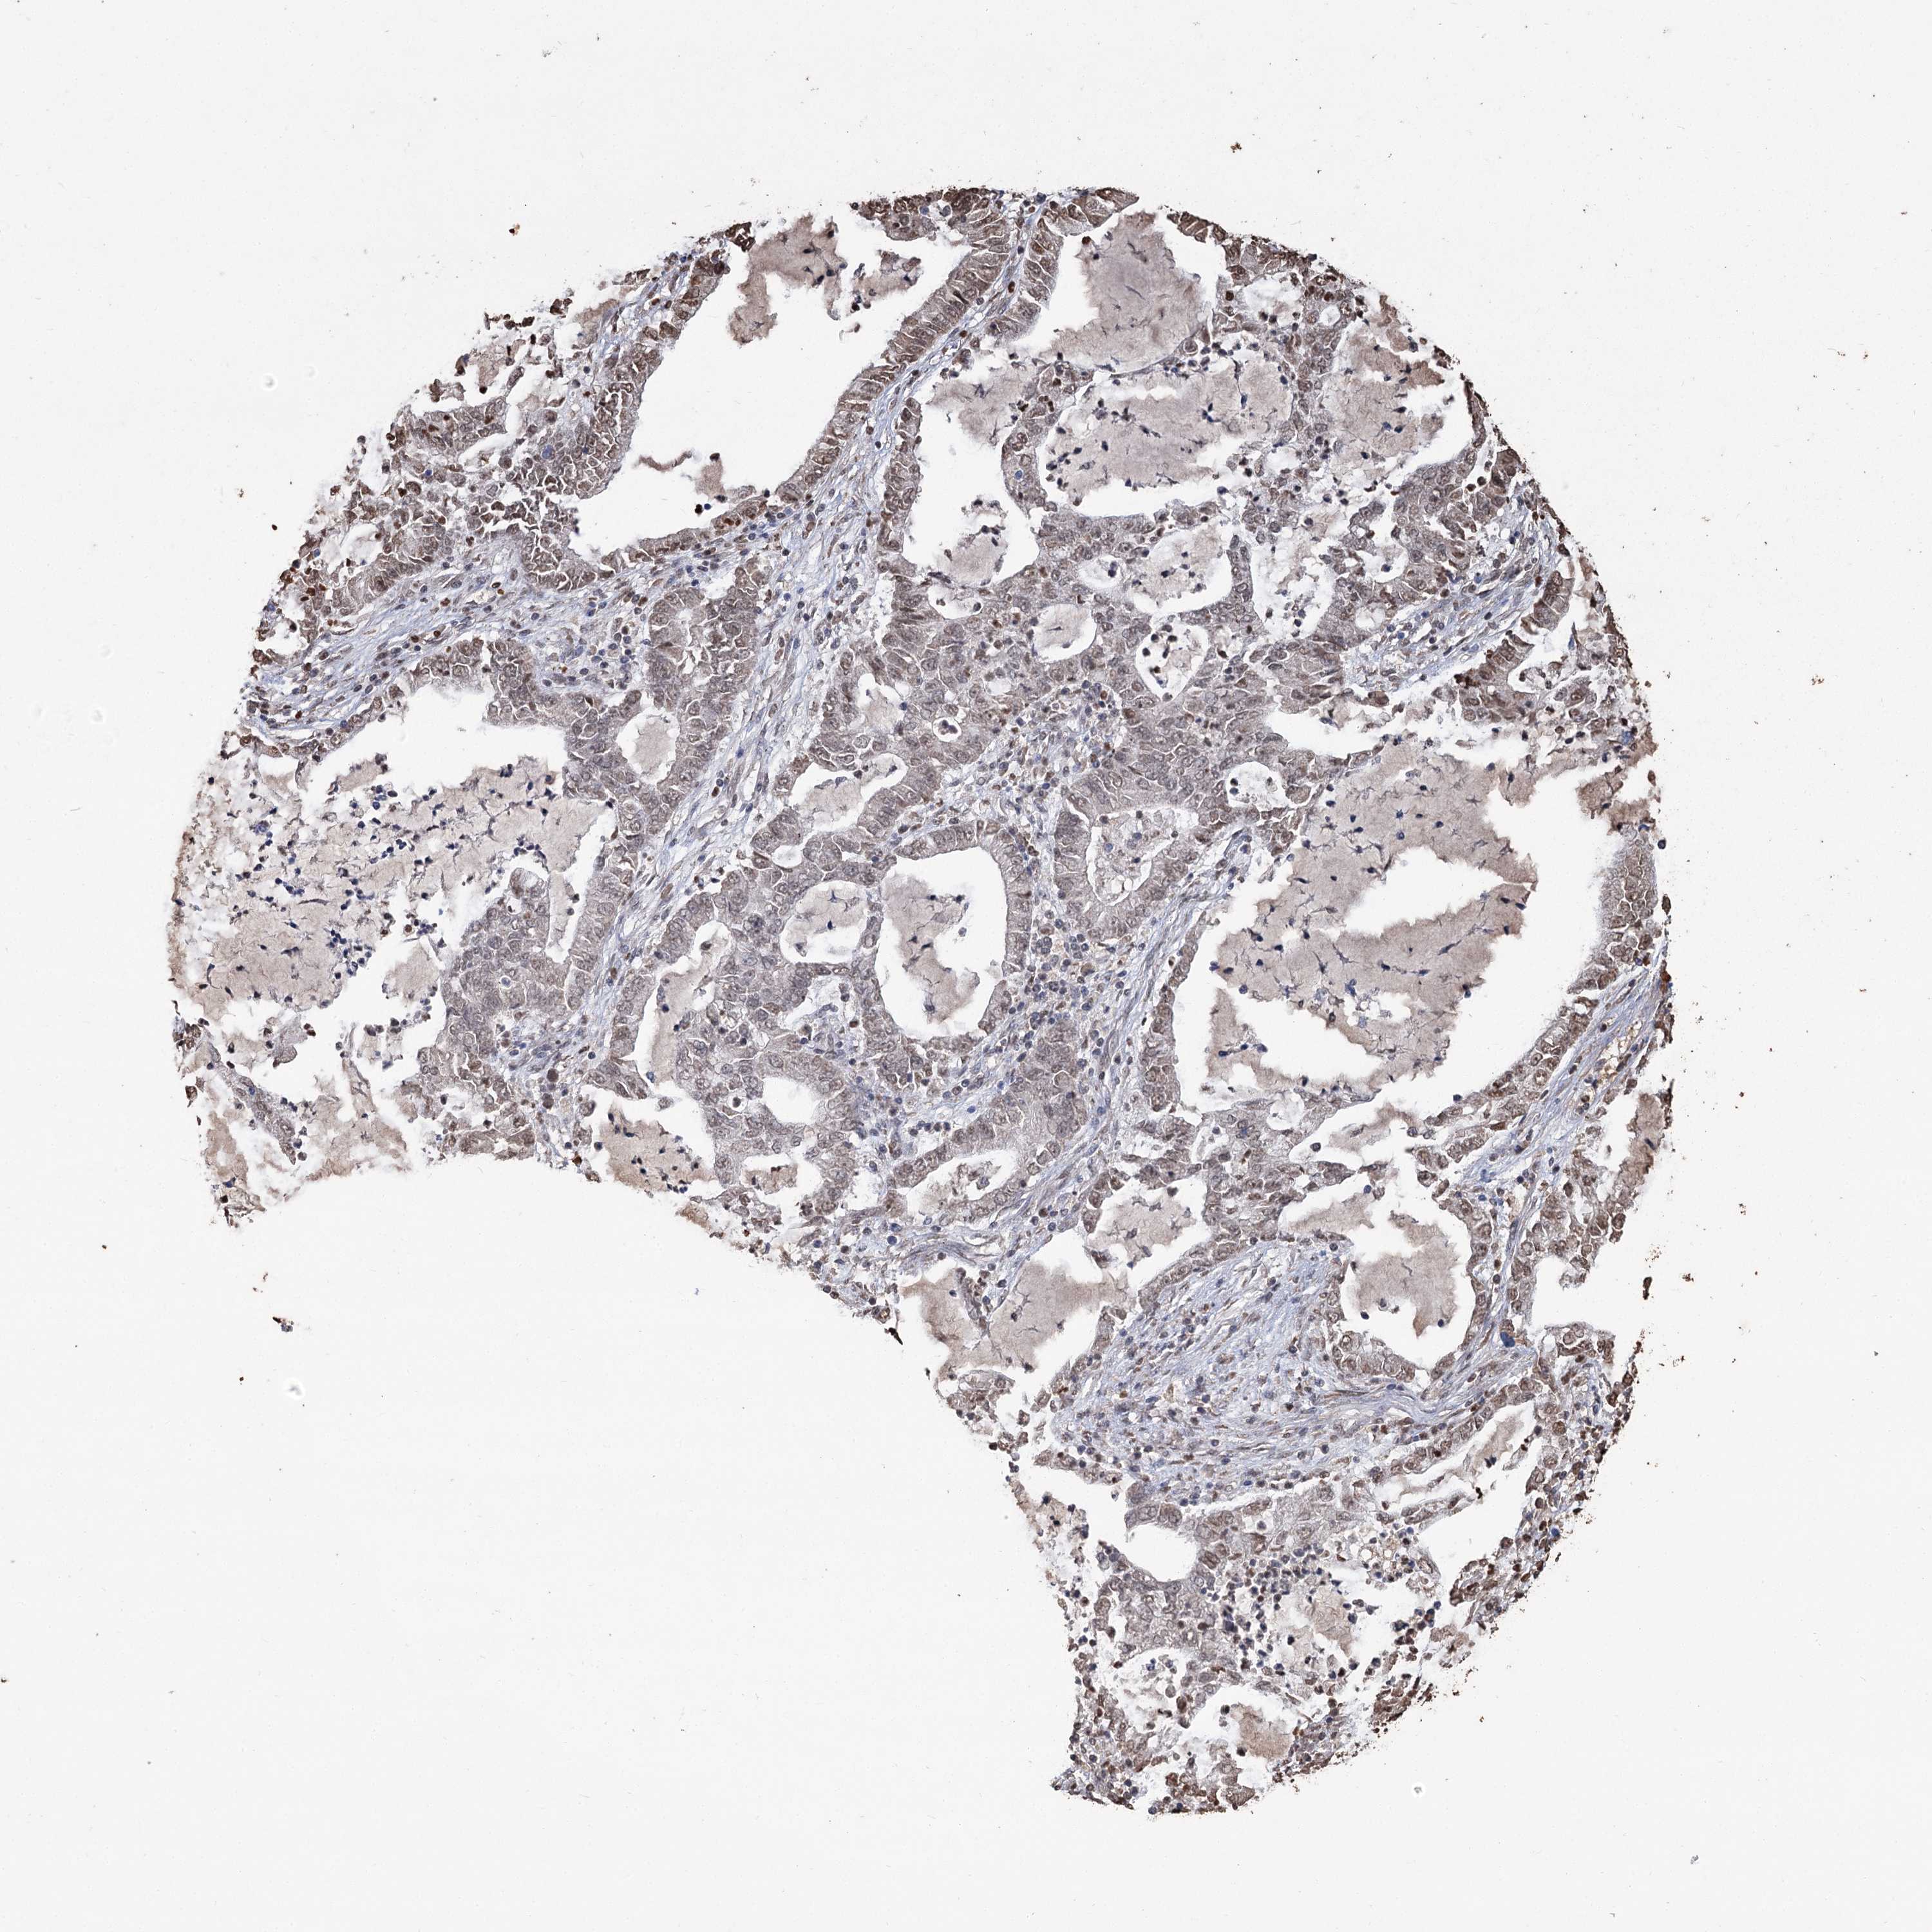

LUNG ADENOCARCINOMA (VALIDATION) - Interactive survival scatter ploti

HBA1 is not prognostic in Lung Adenocarcinoma (validation)

Average pTPM 7.6

Number of samples 105